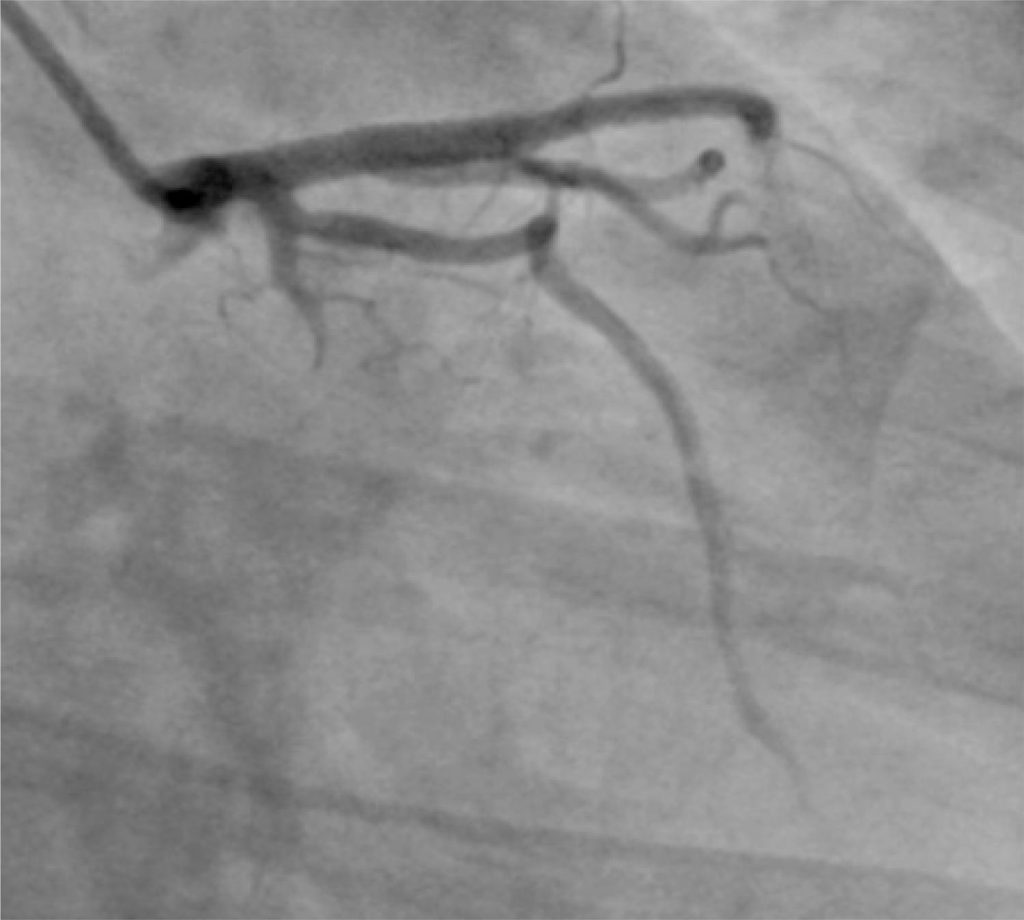

Dissecção coronária espontânea recorrente intra-hospitalar afetando diversas artérias

A dissecção espontânea da artéria coronária é uma causa rara de isquemia miocárdica. Apesar de a primeira descrição ter sido em 1931, o diagnóstico é feito, algumas vezes, tardiamente e/ou erroneamente, devido à falta de conhecimento de suas variações angiográficas não patognomônicas. Além disso, a conduta adequada para esta doença ainda não foi bem estabelecida. Apresentamos um caso raro de recorrência intra-hospitalar de dissecção espontânea envolvendo duas artérias coronárias − descendente anterior e circunflexa −, com distintas apresentações clínicas.